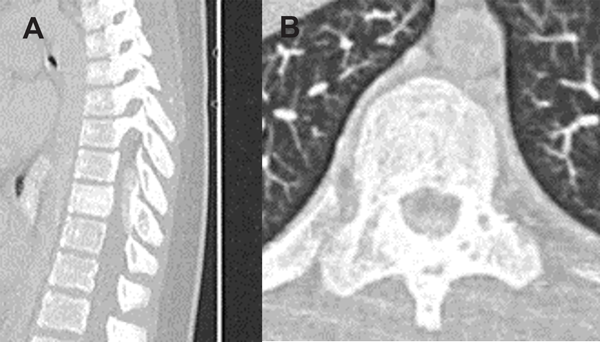

Paciente masculino de 11 años hospitalizado por dorsalgia, paraparesia progresiva severa y retención urinaria. La tomografía computada (TC) y las imágenes de resonancia magnética (RM) revelaron una lesión a nivel D8 y D9, (Figuras 1 y 2). Debido a la rápida progresión de los síntomas se indicó tratamiento quirúrgico al quinto día de internación.

Figura 1. TC prequirúrgica con contraste. A) Corte sagital. B) Corte axial.